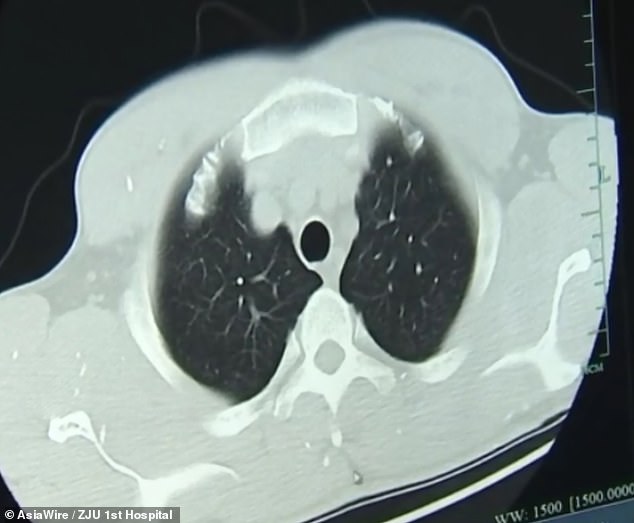

Dr Huang Jianrong, from the Affiliated Hospital of Zhejiang University School of Medicine, ordered brain and chest MRI scans. These revealed that Mr Zhu's brain and chest were riddled with cysts of the pork tapeworm. Dr Huang said: 'He not only had numerous space-occupying lesions in his brain, but he also had cysts in his lungs and chest muscles.' Different patients respond differently to the infection depending on where the parasites occupy.